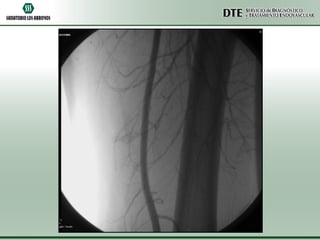

Arteriografía MMII

Arteriografia MMII

•Conclusiones:

•Oclusión completa de arteria poplítea izquierda

•Oclusión de arteria tibial posterior derecha

•Conclusiones: •Oclusión completa dearteria poplítea izquierda •Oclusión de arteria tibial posterior derecha